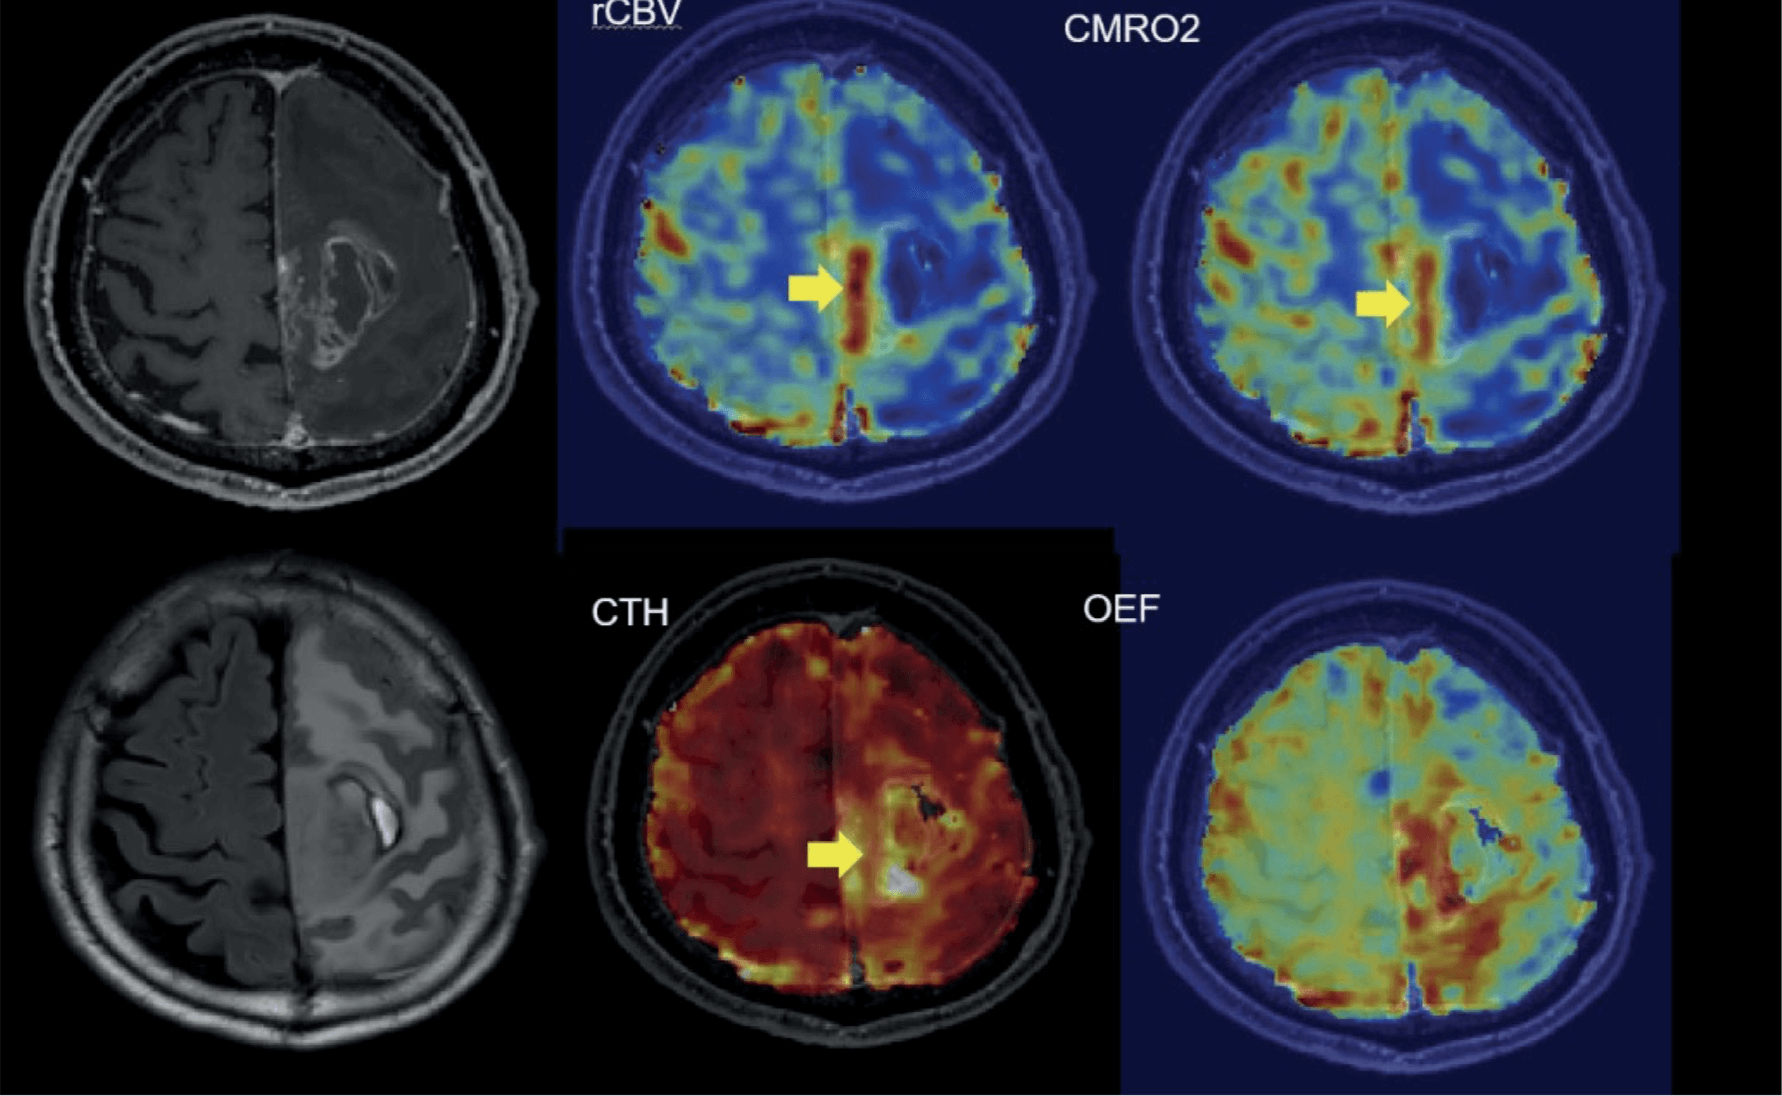

BIOMARCATORI PROPRIETARI PER LA NEURO-ONCOLOGIA

Biomarcatori Vascolari

- CTH Eterogeneità del tempo di transito capillare.

Biomarcatori Metabolici

- OEF Frazione di estrazione dell’ossigeno.

- CMRO₂ Tasso metabolico di consumo dell’ossigeno.